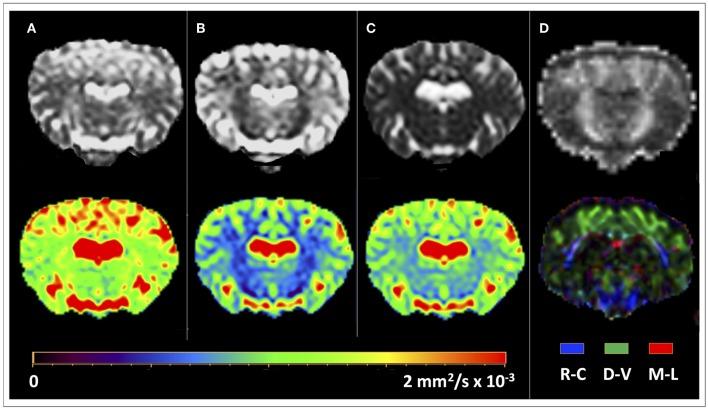

Diffusion Tensor Magnetic Resonance Imaging (DTI) allows to decode the mobility of water molecules in cerebral tissue, which is highly directional along myelinated fibers. By integrating the direction of highest water diffusion through the tissue, DTI Tractography enables a non-invasive dissection of brain fiber bundles. As such, this technique is a unique probe for characterization of white matter architecture. Unraveling the principal brain texture features of preclinical models that are advantageously exploited in experimental neuroscience is crucial to correctly evaluate investigational findings and to correlate them with real clinical scenarios. Although structurally similar to the human brain, the gyrencephalic ovine model has not yet been characterized by a systematic DTI study. Here we present the first sheep () tractography atlas, where the course of the main white matter fiber bundles of the ovine brain has been reconstructed. In the context of the EU's Horizon EDEN2020 project, brain MRI protocol for ovine animal models was optimized on a 1.5T scanner. High resolution conventional MRI scans and DTI sequences (b-value = 1,000 s/mm, 15 directions) were acquired on ten anesthetized sheep , in order to define the diffusion features of normal adult ovine brain tissue. Topography of the ovine cortex was studied and DTI maps were derived, to perform DTI tractography reconstruction of the corticospinal tract, corpus callosum, fornix, visual pathway, and occipitofrontal fascicle, bilaterally for all the animals. Binary masks of the tracts were then coregistered and reported in the space of a standard stereotaxic ovine reference system, to demonstrate the consistency of the fiber bundles and the minimal inter-subject variability in a unique tractography atlas. Our results determine the feasibility of a protocol to perform DTI tractography of the sheep, providing a reliable reconstruction and 3D rendering of major ovine fiber tracts underlying different neurological functions. Estimation of fiber directions and interactions would lead to a more comprehensive understanding of the sheep's brain anatomy, potentially exploitable in preclinical experiments, thus representing a precious tool for veterinaries and researchers.

扩散张量磁共振成像(DTI)能够解析脑组织中水分子的移动性,水分子在有髓纤维上具有高度的方向性。通过整合穿过组织的最高水扩散方向,DTI纤维束成像能够对脑纤维束进行非侵入性剖析。因此,这项技术是表征白质结构的独特探针。揭示临床前模型的主要脑纹理特征对于正确评估研究结果并将其与实际临床情况相关联至关重要,这些特征在实验神经科学中得到了有效利用。尽管与人类大脑在结构上相似,但尚未通过系统的DTI研究对回脑羊模型进行表征。在此,我们展示了首个绵羊()纤维束成像图谱,其中重建了羊脑主要白质纤维束的走行。在欧盟“地平线2020”项目EDEN2020的背景下,在1.5T扫描仪上优化了羊动物模型的脑MRI方案。对十只麻醉的绵羊进行了高分辨率常规MRI扫描和DTI序列(b值 = 1000 s/mm²,15个方向)采集,以确定正常成年羊脑组织的扩散特征。研究了羊皮质的地形并生成了DTI图谱,以便对所有动物双侧的皮质脊髓束、胼胝体、穹窿、视觉通路和枕额束进行DTI纤维束成像重建。然后将这些纤维束的二元掩码进行配准,并报告在标准立体定向羊参考系统的空间中,以在独特的纤维束成像图谱中展示纤维束的一致性和最小的个体间变异性。我们的结果确定了对绵羊进行DTI纤维束成像方案的可行性,提供了主要羊纤维束的可靠重建和三维渲染,这些纤维束是不同神经功能的基础。纤维方向和相互作用的估计将有助于更全面地理解羊的脑解剖结构,有可能在临床前实验中得到应用,从而为兽医和研究人员提供了一个宝贵的工具。